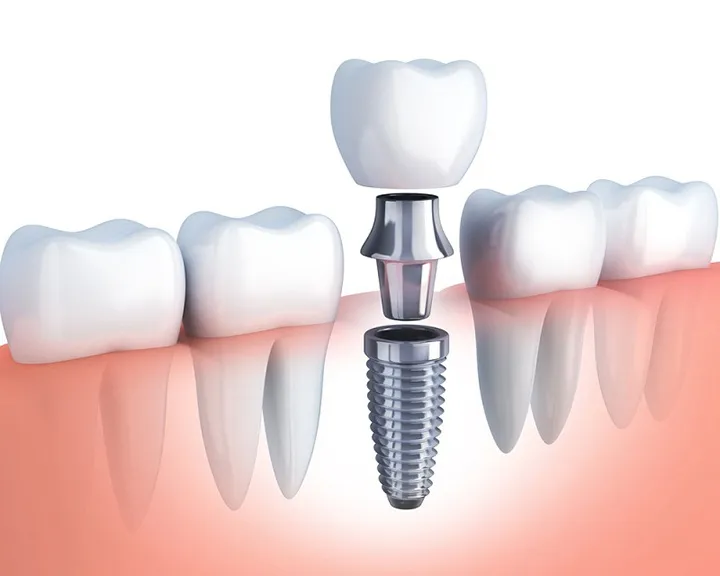

Răng hàm đóng vai trò quan trọng trong việc nhai thức ăn, giúp nghiền nhỏ thức ăn trước khi nuốt. Mất răng hàm có thể làm giảm đến 70% khả năng nhai của hàm, vì vậy việc bảo tồn răng hàm luôn được ưu tiên trong điều trị nha khoa.

- Nhổ răng không làm giảm tuổi thọ: Nếu không trồng răng giả sau khi nhổ, có thể dẫn đến tiêu xương và thay đổi khuôn mặt, gây ra hiện tượng lão hóa. Điều này dễ gây hiểu lầm rằng nhổ răng làm giảm tuổi thọ.